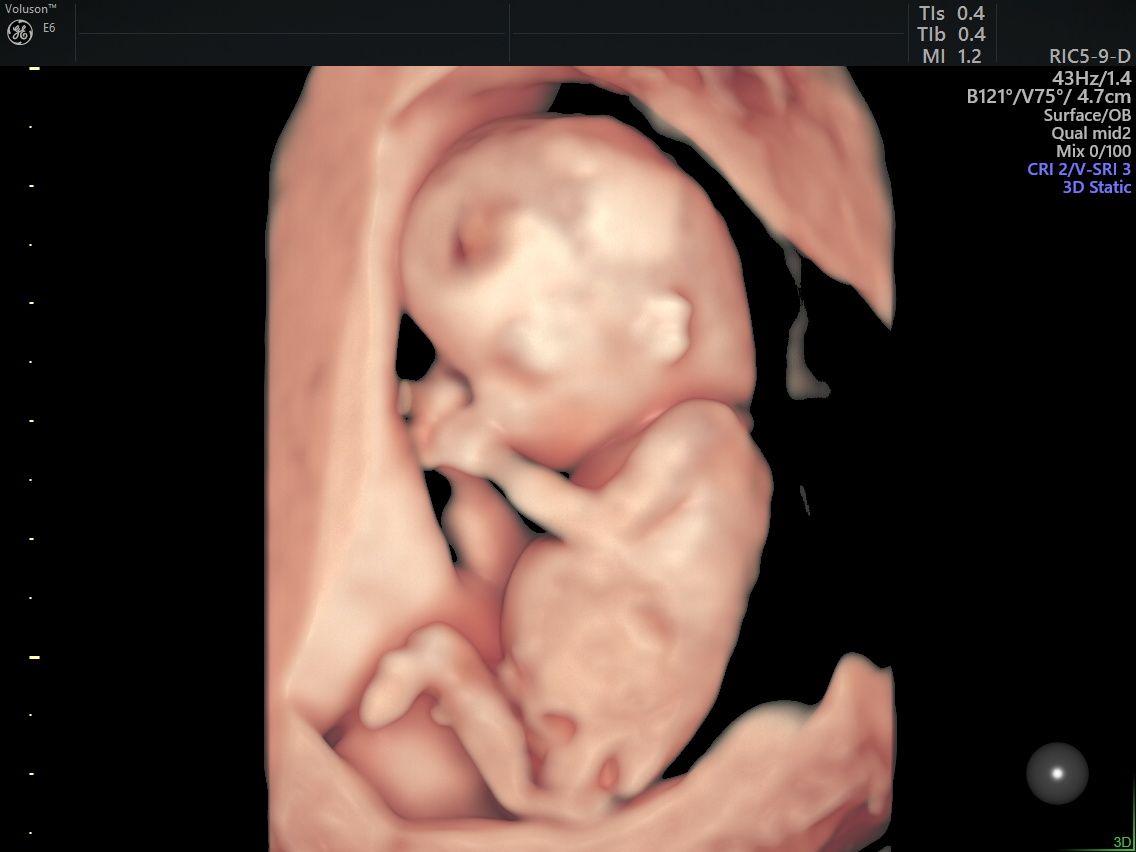

Realizo estudios con tecnología avanzada para detectar posibles complicaciones durante el embarazo. Entre ellos se incluyen ultrasonidos de tamizaje en el primer trimestre, ultrasonidos estructurales, seguimiento de embarazos gemelares y pruebas genéticas como ADN fetal, biopsia de vellosidades coriales y amniocentesis, que ayudan a evaluar la salud del bebé y del embarazo.